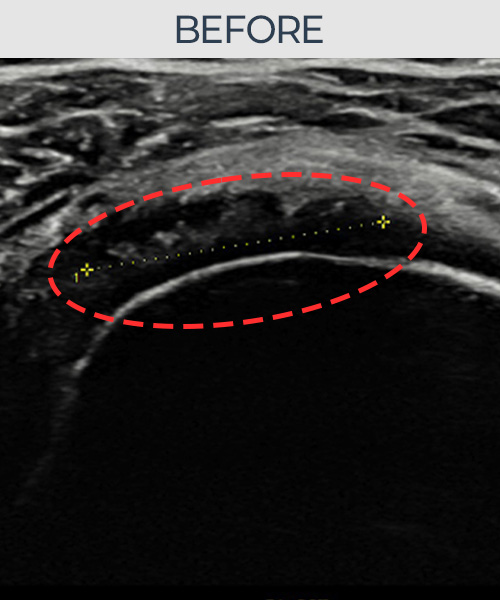

수천건의 수술 경험을 바탕으로 정확히 진단하여

인대파열을 비수술로 치료합니다.

플래티넘정형외과에서는 수술이 필요없는 인대파열만을

정확히 진단하여 특허받은 술기로 비수술로 치료합니다.